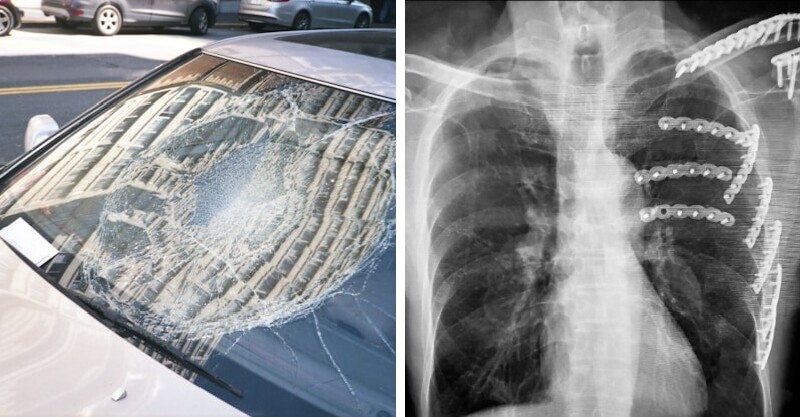

不敢過馬路...小樹懶「緊抱護欄」和警察叔叔求救 「無辜對視」好呆萌:可以送偶回家嗎~ 鴨嘴獸泰瑞 2021-09-28 檢舉 樹懶動作真的是出了名的緩慢,這樣繁忙的道路對牠們來說真的非常危險,幸好這隻小樹懶有遇到好心的警察叔叔,相關單位事後也發出好消息表示小樹懶已經平安回到家園,之後真的要小心啦!來源:Novo Advertisements 小樹懶抱住護欄的模樣實在是讓人融化,真的超想抱緊處理,也謝謝好心的警察叔叔救了牠!來源:Novo Advertisements 回首頁 2/2 Advertisements 編輯精選推薦 More + 恐發生規模9巨震!網急問「國外遇地震怎麼辦?」 專家曝「3件事必做保命」:快打這電話 宜蘭24歲警重傷!緊急送醫「不樂觀恐截肢」 家屬「怒轟兇手1事」:泯滅人性 台中70歲老翁「撞斷肋骨」!醫見X光「見更可怕殺手」意外救了一命 太殘忍!爸媽「把兒子的寵物煮熟」端上桌猛嗑 小朋友得知後「反應惹怒全網」:以後會有報應 快訊/圖書館「驚傳崩塌」死傷人數曝光!警消直言:「搜救相當困難」 被渣男狠傷單身20多年!65歲惠英紅突宣布「我當媽了」 曬出女兒照感動喊:「她非常非常可愛❤️」 才準備拚特考!台東驚傳「祖孫路邊雙亡」 鎮公所同事悲痛:「他很善良憨厚...」 知名手搖店爆虐狗!15歲失智柯基「被老闆痛打」:把妳安樂死 網友氣炸「議員出手了」 跪地求饒沒用!檳榔攤老闆娘「遭砍3刀身亡」 友震驚「才花錢保釋兇嫌」:恩將仇報 住進深海鳳梨裡!奶油黃「夢幻海綿寶寶浴室」可愛到不真實 波浪門內「連淋浴區都有巧思」療癒翻❤️ 香港大火160死!70歲周潤發被爆「身價百億零捐款」 挨轟「祈福哽咽是演戲」他不忍全說了 6歲童長膿癬永久禿頭!醫檢查驚「兇手竟是牠」小孩易感染 衣服從來不重複!巧手媽「天天替女兒換上蘿莉裝」超華麗 正面一轉「精緻五官+韓妞時裝」Q翻天❤️ 首度曝光!北海道棕熊攻擊「受害者手錶GPS軌跡」 停止一晚後「突然詭異拖行」震驚當地人 女網紅減肥「只吃雞胸肉+花椰菜」!半年後「這器官大面積壞死」 惡霸犬逃家!84歲翁遭狂咬「警開19槍才制止」 急送醫「搶救1個月不治」 男子突發腦出血走了!醫生怒斥:「吃降壓藥時候,沒有注意這3點!」 想包起來咬一口!療癒滿分「寶寶白菜小被被」爆紅育兒界 另一款「大白菜萌娃包巾」畫面更融化❤️ 飛機驚傳墜機!撞上高速公路「直接砸中車子」 畫面曝光「車頂被削成一半」 最新/賈靜雯深夜慟曝「她已離世」 淚PO合照喊:真的好愛你... 女子大火逃生「先救2毛小孩」感動全網!最後結局曝光「另一隻沒這麼幸運」